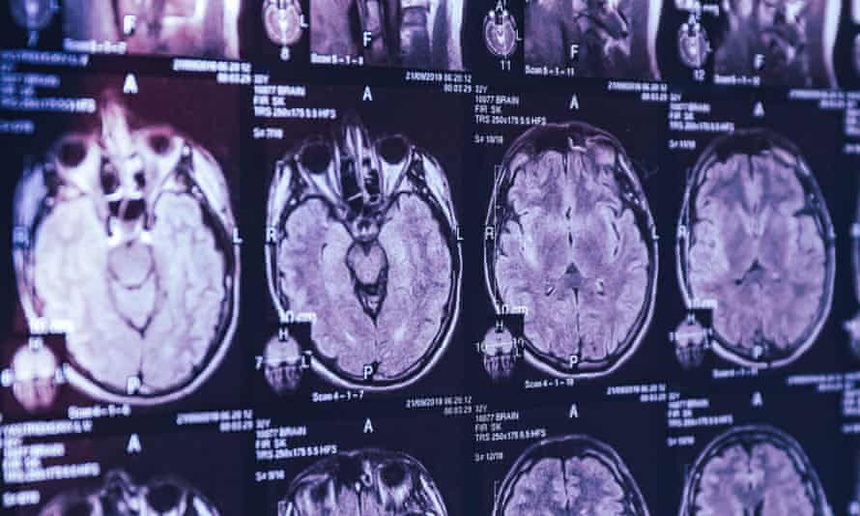

Bối rối trước tình trạng các bệnh nhân, bác sĩ Marrero đã yêu cầu tiến hành nhiều hình thức kiểm tra như xét nghiệm máu, chọc dò tủy sống, chụp cộng hưởng từ và điện não đồ.

Kết quả kiểm tra cho thấy những dấu hiệu bất thường như teo não, rối loạn chức năng thần kinh. Tuy nhiên, các mẫu xét nghiệm không có đủ tính liên kết để giúp các chuyên gia y tế đưa ra một chẩn đoán rõ ràng.

Phát hiện dấu hiệu bất thường trong ảnh chụp não của các bệnh nhân. Ảnh: Guardian.